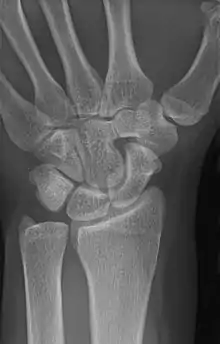

Carpal coalition

An example of a lunotriquetral coalition, the most commonly fused carpal bones

The lunate and triquetral bones are the most common carpal bones to fuse together, resulting in a lunotriquetral coalition in 1% of people. 60% of patients with a lunotriquetral coalition will have it bilaterally.[1] Among isolated incidents the capitate and hamate bones are the next most common to fuse followed by the pisiform-triquetrum, trapezium-trapezoid, scaphoid-capitate, and triquetrum-hamate.[3]